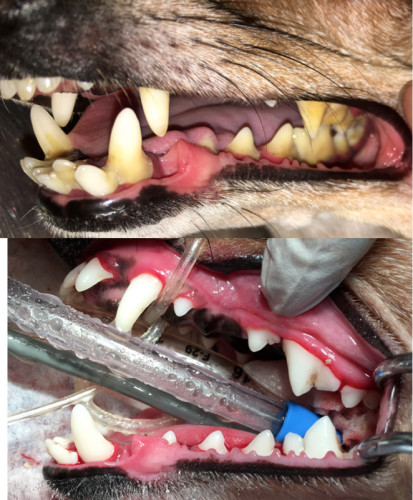

症例写真